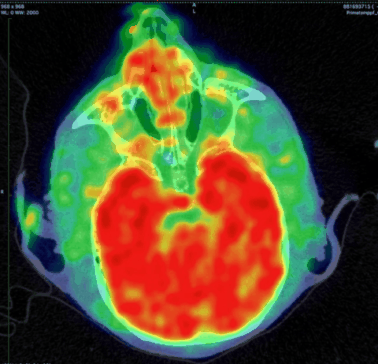

CASE 4: NHP brain PET/CT dynamic DOPA imaging

workimg

• Courtesy of: CERMEP, Lyon, France

Research objective: Investigation of DOPA uptake in NHP brain

Animal model: NHP, ~ 3 kg

Acquisition protocol: PET imaging: 90 min acquisition, injection right after acquisition starts. CT imaging: 80kV, 40s

Processing and reconstruction protocol: PET: 3D OSEM, 9x 10 min, 0.84 mm isotropic voxel size. CT: 0.15 mm isotropic voxel size

Biomarker or contrast agent: 18F-DOPA, ~ 3 mCi